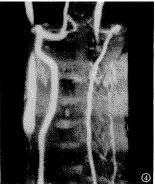

运用Siemens Magneton Vision 1.5T超导型MR扫描仪,颈部相控阵线圈。首先采用二维快速自旋回波技术进行颈椎矢状成像,在颈椎2~3椎间隙平面应用K-空间分段MR电影相位对比(segmented K-space cine phase-contrast MR)序列垂直于椎动脉扫描。采用心电门控技术,平静呼吸,TR为29ms,TE 7ms,翻转角30°,根据心电图R-R间期不同,每节段K-空间相位编码分别为7,9,11,层厚6mm,无间隔,矩阵为196×256,FOV 10cm,在心脏舒张期末至收缩早期采集信号,流速编码(venc)150cm/s。椎动脉血管造影采用常规3D-TOF法(图1)。

图1 正常椎动脉的3D-TOF MRA成像示双侧椎动脉形态基本对称,形态自然